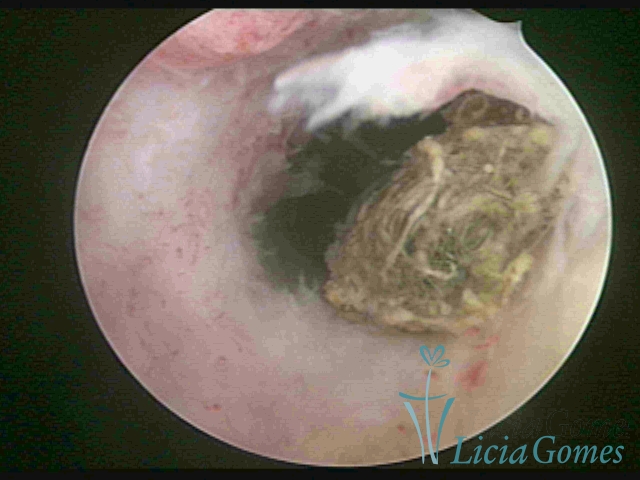

IUD waste material in the uterine cavity